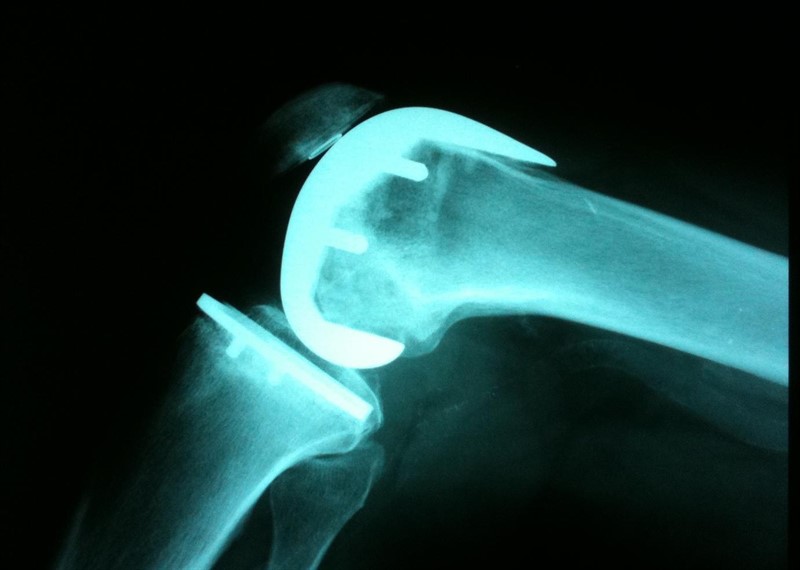

Resultados relevantes para el paciente de reemplazo de rodilla unicompartimental versus total

BMJ, 21 de febrero de 2019 El reemplazo de rodilla unicompartimental (RRU) o el reemplazo total de rodilla (RTR) son opciones viables para el tratamiento de la osteoartritis unicompartimental aislada. Al comparar directamente los dos tratamientos, el estudio demuestra mejores resultados para RRU en varios dominios de resultados. Sin embargo, el riesgo de cirugía de revisión fue menor para la RTR. Esta información debe estar disponible para los pacientes como parte del proceso compartido de toma de decisiones al elegir las opciones de tratamiento.